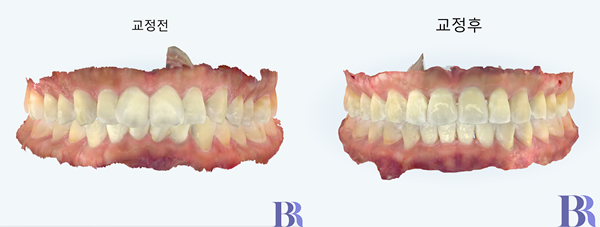

치료 후 변화

치료 종료후 정면 모습을

비교해보았습니다.

과개교합도 잘 해결되고

치아 배열도 가지런해졌네요.

이 치료의 성공 열쇠는

앞니가 지금보다 튀어나가지

않게 하는 것입니다.

위 앞니 치아의 각도가

처음에 비해서 줄어들었고

그만큼 더 좋아졌지요.